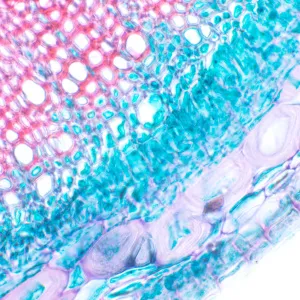

Микроскоп MAGUS Bio 230B предназначен для лабораторной и научно-исследовательской работы с биологическими образцами в виде тонких срезов или мазков. Наблюдения ведутся в светлом поле в проходящем свете, при необходимости микроскоп можно оснастить дополнительными принадлежностями для использования методов темного поля, поляризованного света и фазового контраста. Микроскоп найдет применение в сферах фармацевтики, медицины, биотехнологии, охраны окружающей среды, криминалистики, сельского хозяйства.